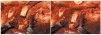

Minimal access spinal surgery has been moving forward in recent years and will therefore be covered in more detail in this review. Thoracoscopy (Figure 5) has been introduced as a new therapeutic approach for treating spinal pathology. The endoscope was first used in surgery on the spine in 1993, when it was considered an alternative to "open surgery." At first it was used mainly in patients considered to be at high risk from thoracotomy, given that the minimal procedure is less traumatic for the chest wall.18 Time has shown, however, that the deformity must be elastic and the angle greater than 75º if maximum benefit is to be derived from thoracoscopy. The technique should not be used in patients in whom a lung must be collapsed, who have severe respiratory insufficiency, who require high positive pressures to maintain adequate ventilation, or who have pleural adhesions. For the past 7 years, an anterior endoscopic approach has been used for spinal release surgery (with the purpose of increasing flexibility), for anterior arthrodesis, for epiphysiodesis (to prevent a flat back or the crankshaft problem), and for disk resections. It has also been used to treat certain primary tumors, spinal metastases, and fractured or herniated disks.

Figure 5. An artist's depiction (a) and a surgical image (b) of thoracoscopy.